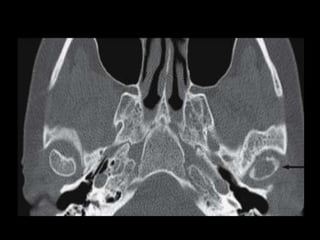

Coronal CT scan in bone windows. White arrows indicate bilateral condyle fractures

with medial displacement